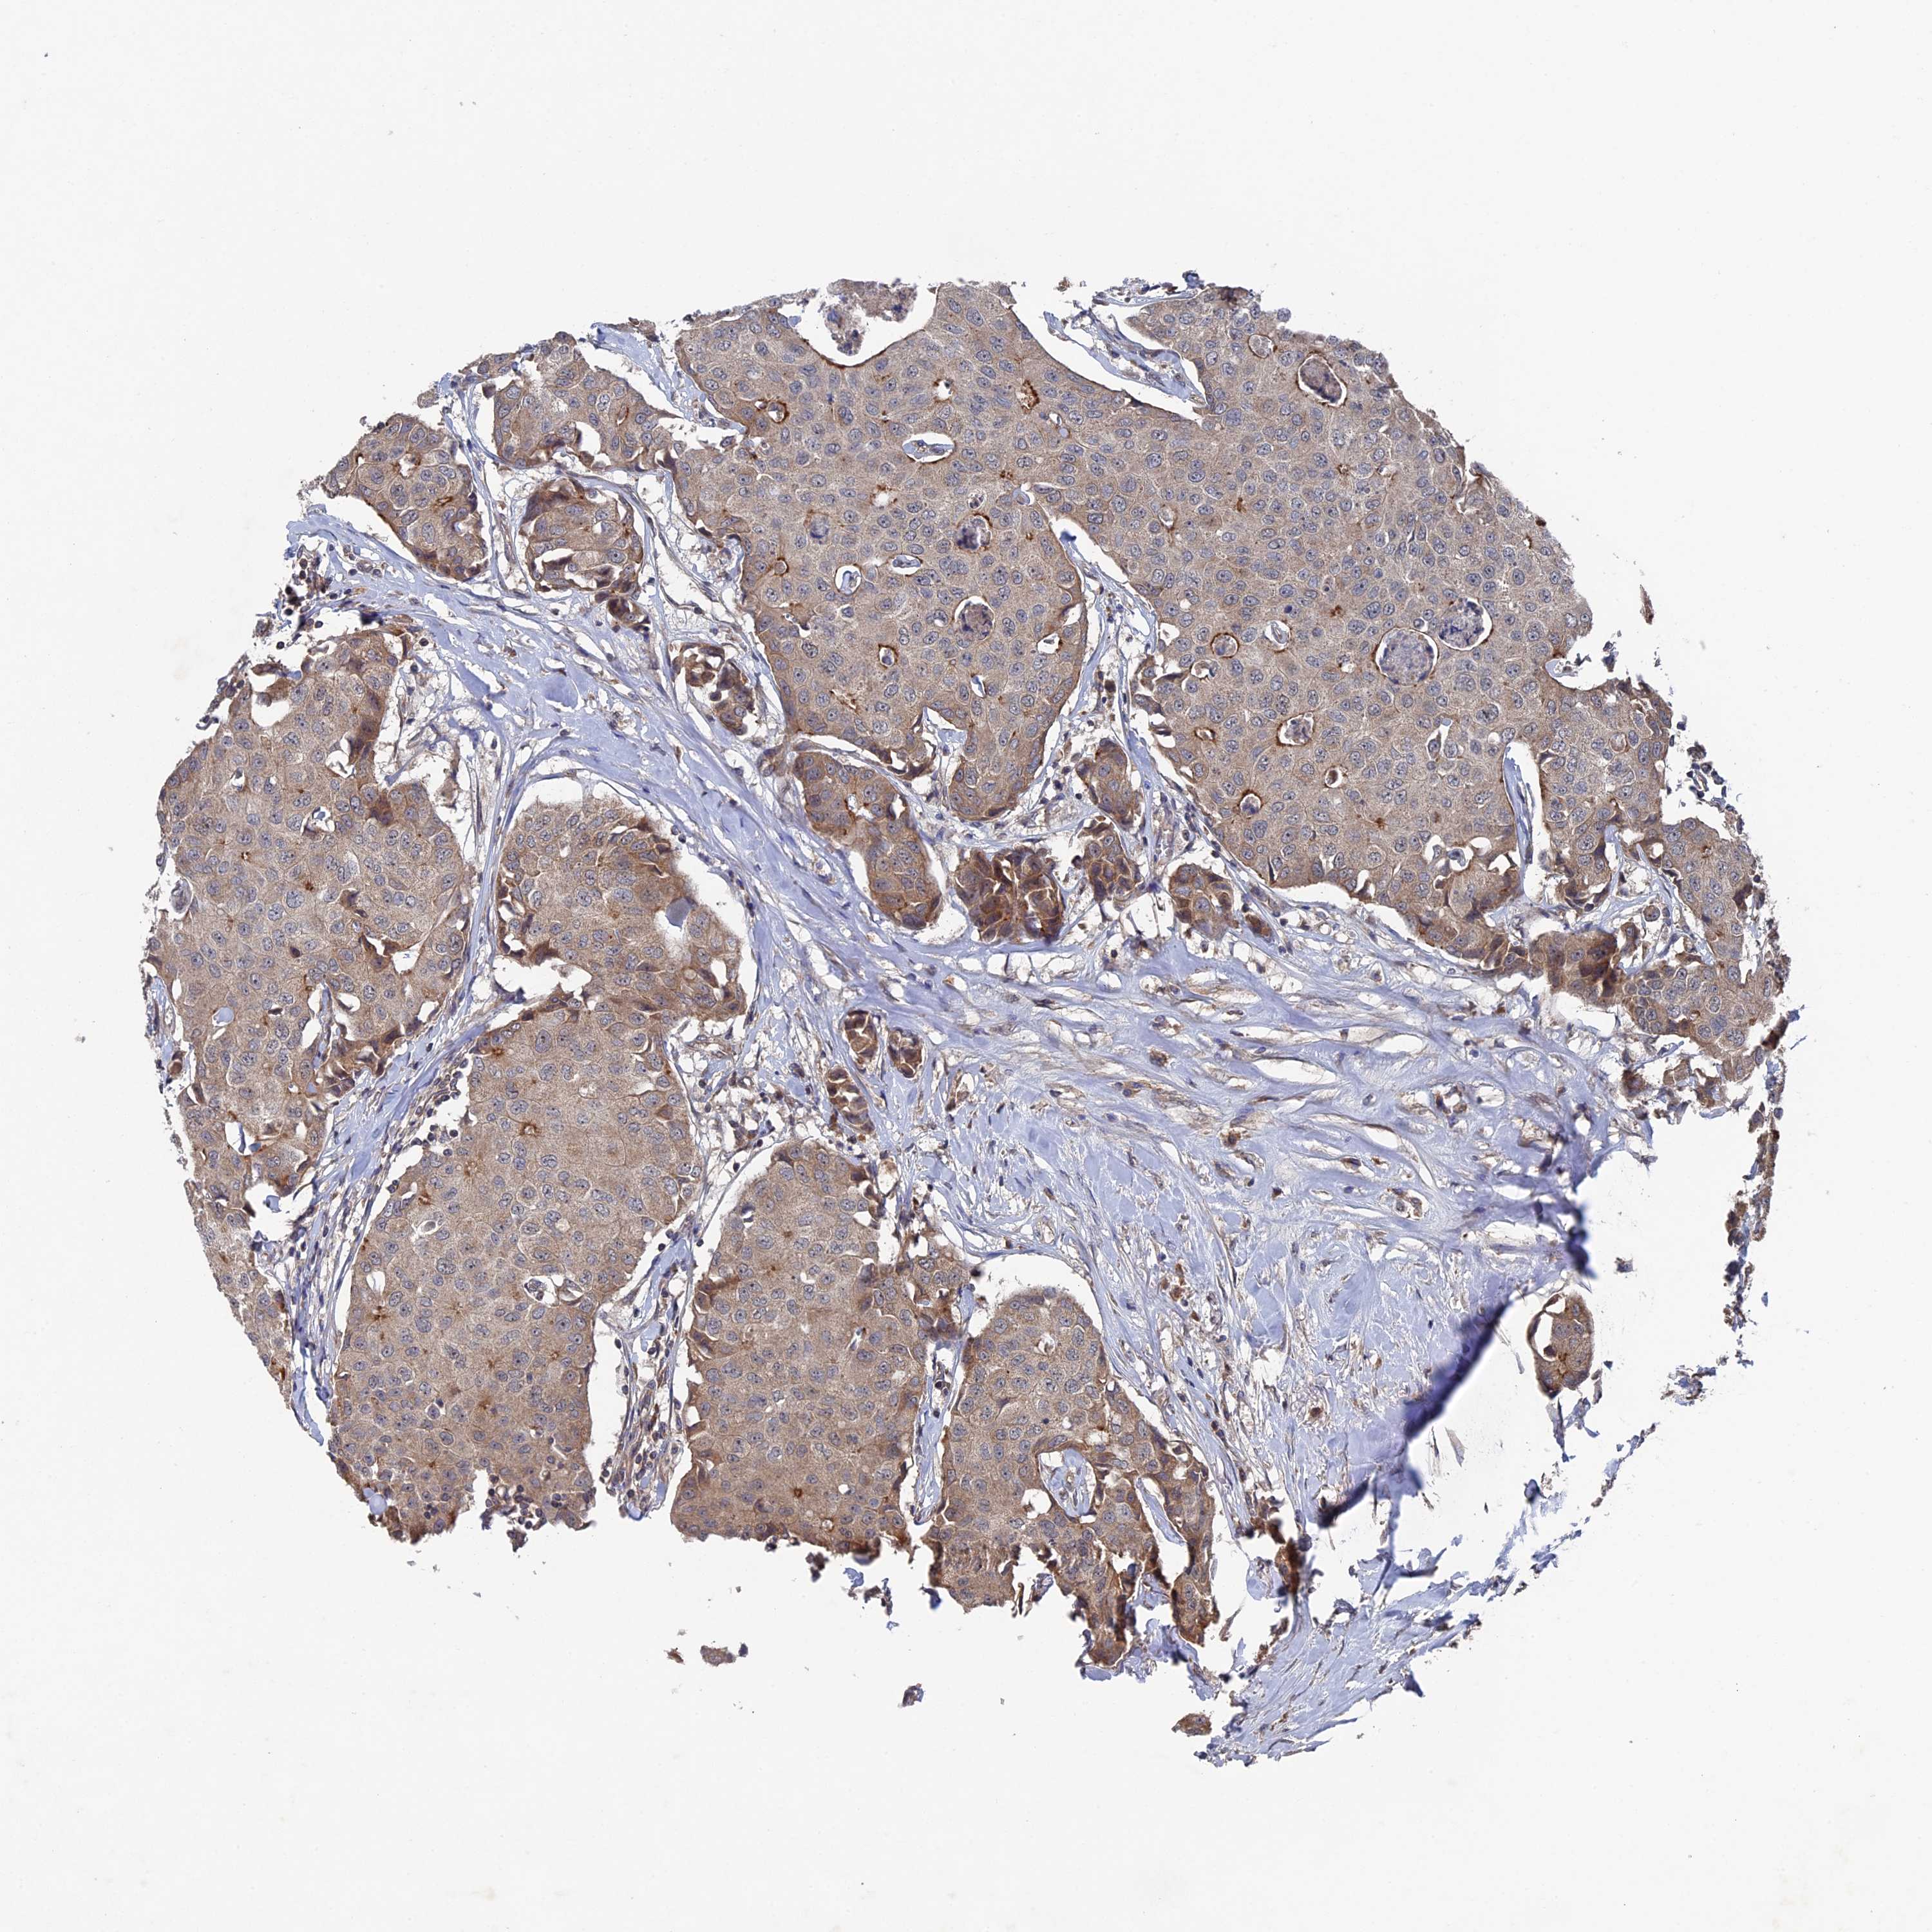

BRCA TCGA BRCA VALIDATION PROTEIN EXPRESSION